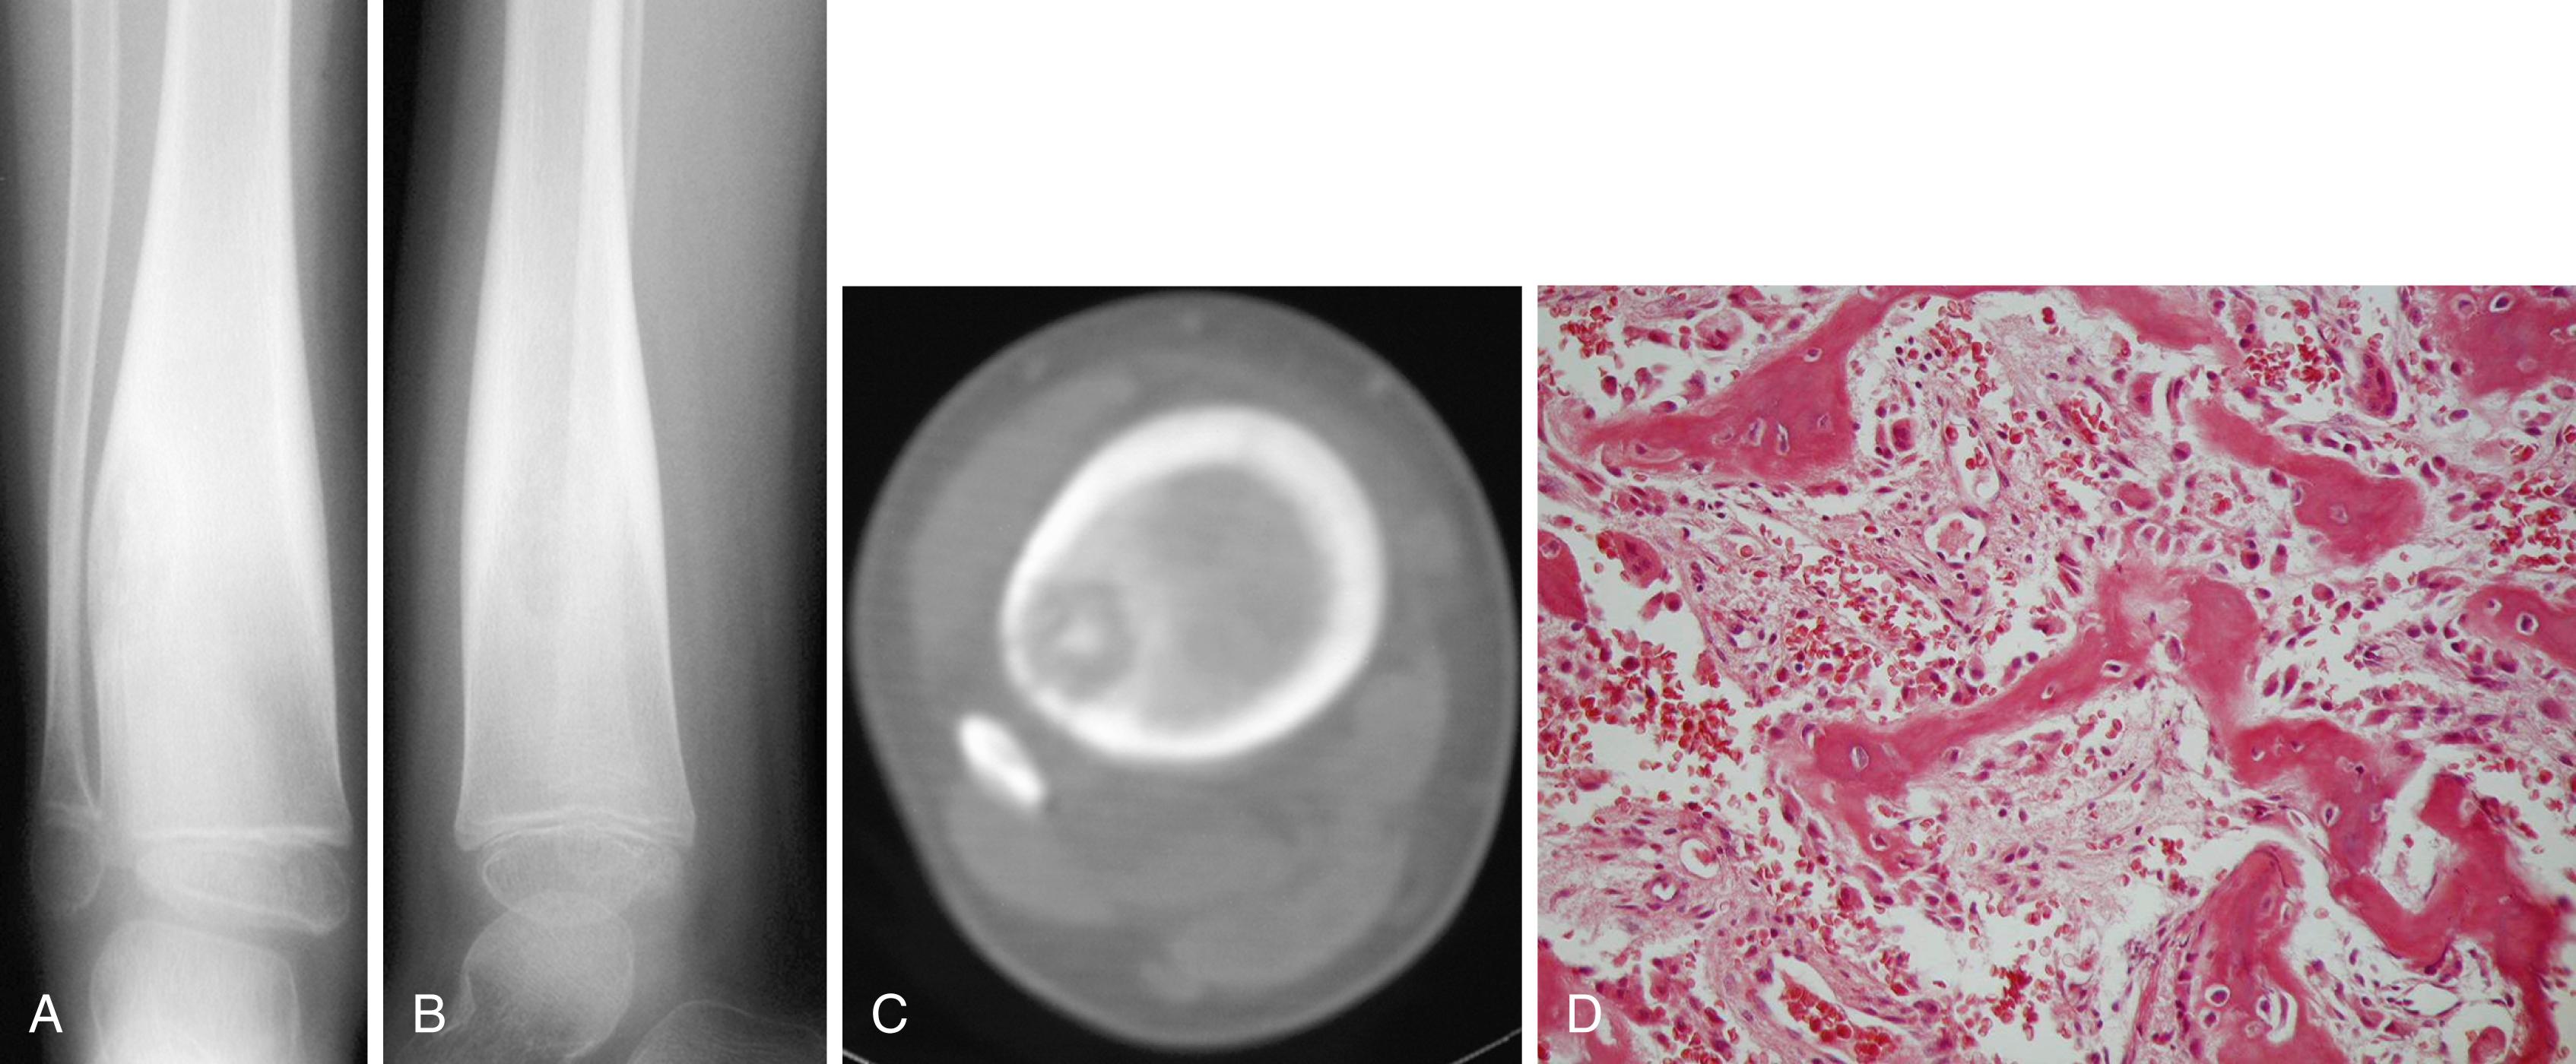

FIGURE 26.15, Four-year-old boy with a 1-year history of right leg pain.

FIGURE 26.18, A, Solitary eosinophilic granuloma of femoral diaphysis causing severe periosteal reaction. B and C, Low-power and high-power photomicrographs demonstrate Langerhans cell histiocyte and eosinophils.

Microscopically, the diagnosis is made by the identification of Langerhans cells. The Langerhans cell is a large histiocytic cell with an indented nucleus, a crisp nuclear membrane, and abundant eosinophilic cytoplasm. The cells stain positively for S-100 protein. The lesion also contains multinucleated giant cells and other inflammatory cells, including clusters of eosinophils. Electron microscopy may identify characteristic organelles in the Langerhans cell cytoplasm called Birbeck granules.